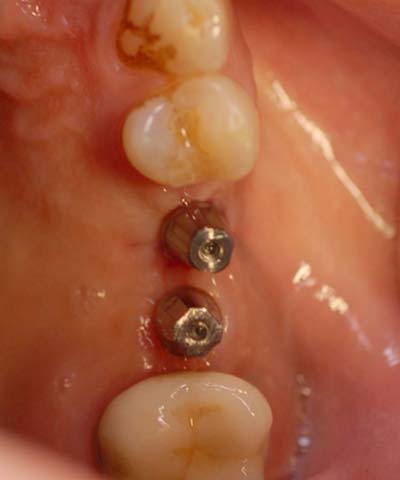

鼻竇增高術(側窗) 首頁 案例分享 人工植牙 鼻竇增高術(側窗) 鼻竇增高術(側窗) 製作多年的牙橋,牙根斷裂,發炎 鼻竇增高術 側面開窗 抬高鼻竇 鼻竇增高術 置入骨粉 覆蓋再生膜,保護骨粉 術後追蹤,傷口良好 裝戴正式假牙 完成 8年追蹤 左上牙根斷裂 植牙重建 九年追蹤